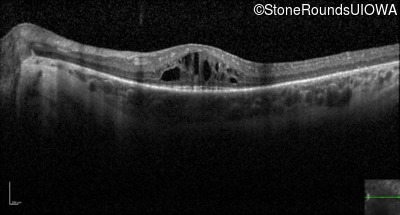

Optical Coherence Tomography - Right - 20/80 +2

Exemplar / OCT Stack